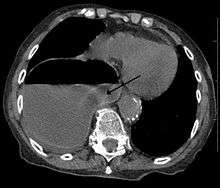

A right sided diaphragmatic hernia with the stomach in the chest (left side of image marked by the arrow). Note the air fluid level in the stomach.

Diagnosis can be made by either CT or Xray.